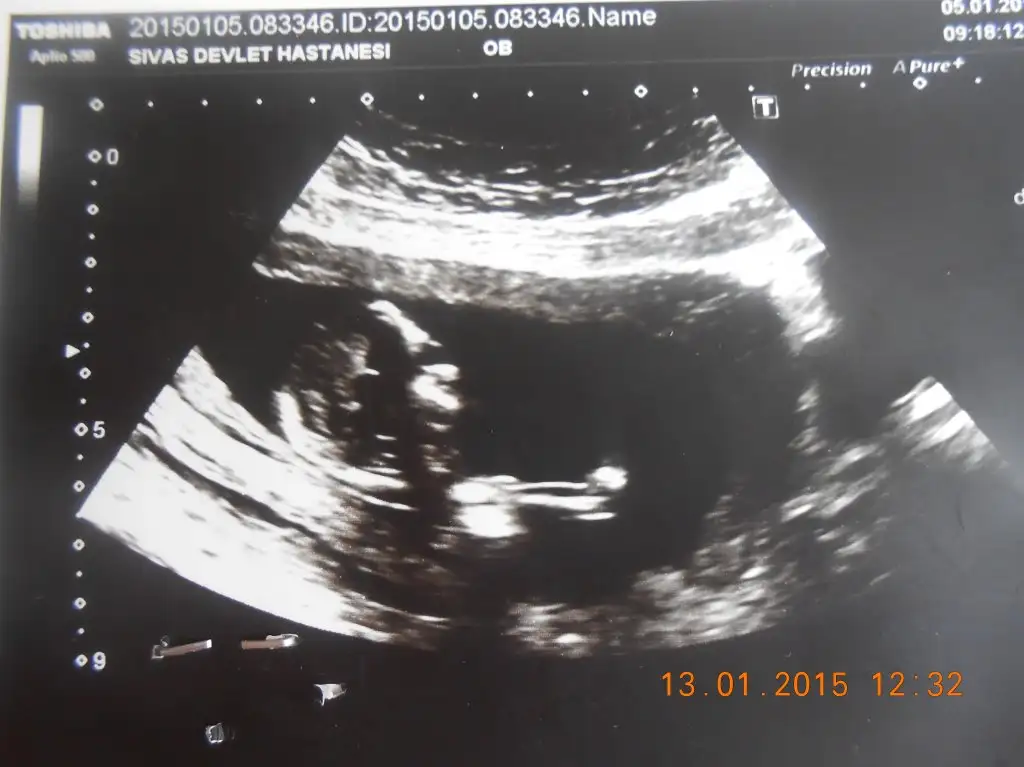

Benim bebisin cinsyeti ne olabilir acaba :))

Acaba benim bebegin cinsiyeti nedir sizce arkadaslar bana kiz gibi geldi :))